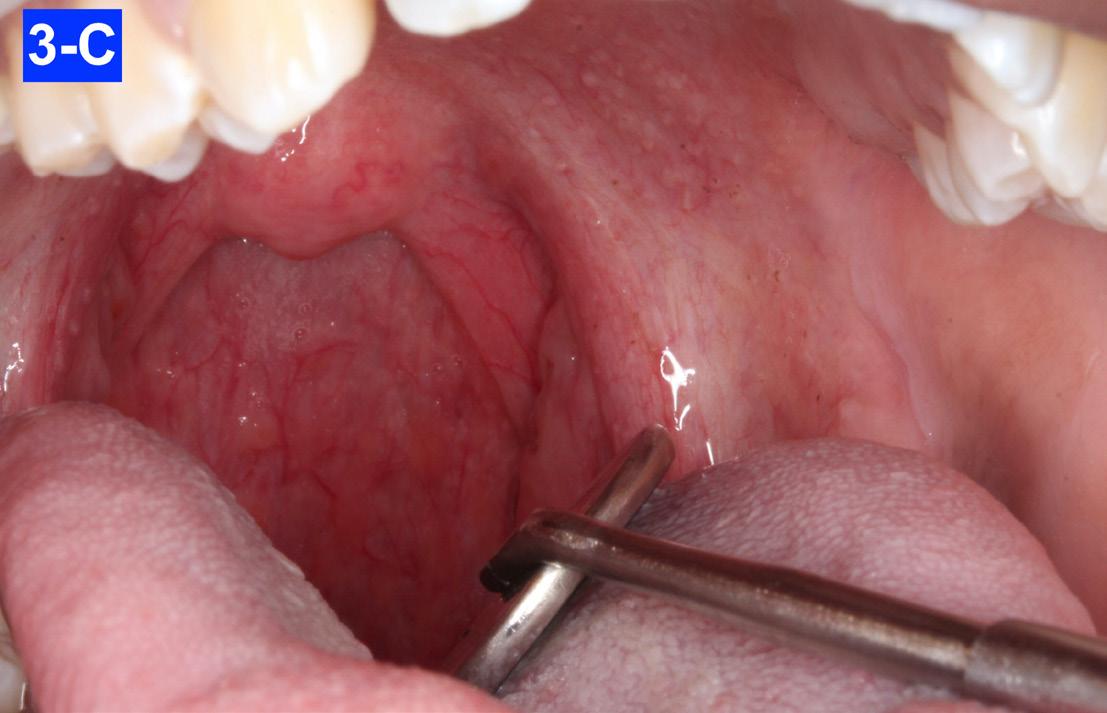

Clinical appraisal of the airway revealed a patent airway: Pharynx - 10/10 mm, Oropharynx - Mallampati IV, Nasopharynxvery patent (Figures 3-A, B, C, D, E).

Fig. 3-C: Oropharynx II

Fig. 3-B: Oropharynx I